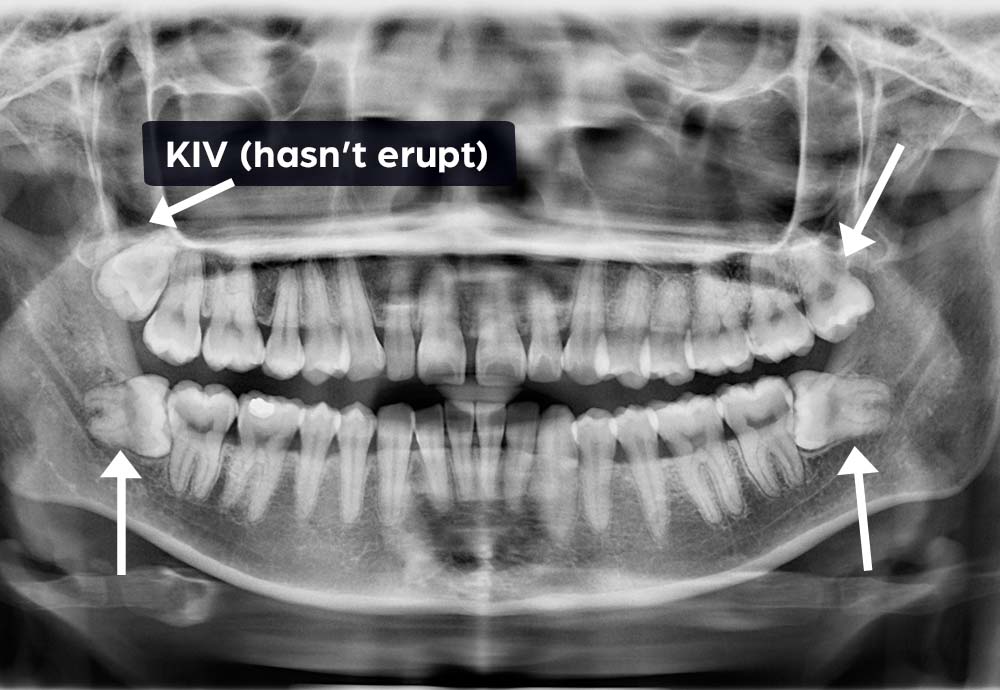

Some lower wisdom teeth can be close to the inferior alveolar nerve (which gives feeling to your lip & chin).

In rare cases, this may cause temporary symptoms such as:

These effects are usually temporary

Wisdom tooth removal is generally safe, but like any surgical procedure, there are some risks such as nerve irritation and infection.

In rare cases, lower wisdom teeth may be close to a nerve, which could cause temporary numbness. To improve safety, we use Piezo-assisted surgery and laser disinfection, which help protect nearby tissues and support faster healing.